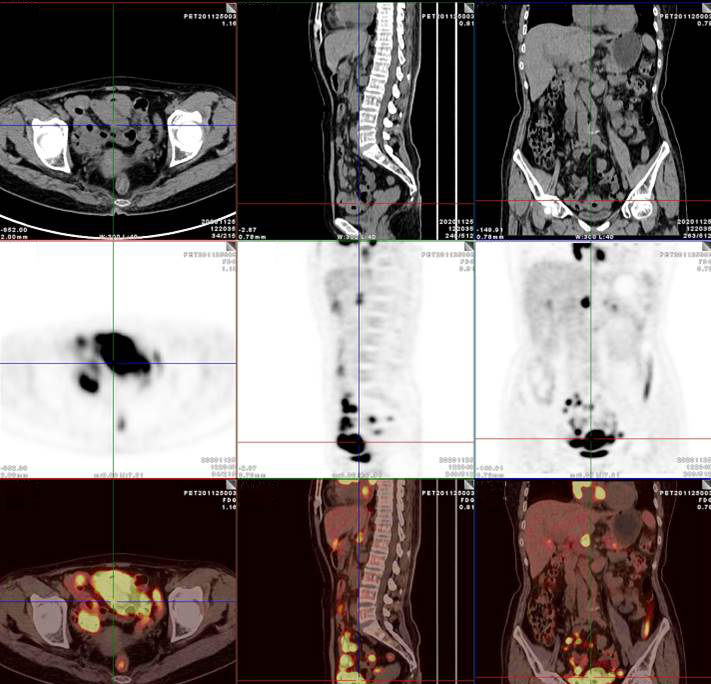

PET/CT影像圖

左/右心房病灶放射性攝取明顯增高

腸系膜多發(fā)淋巴結(jié)放射性攝取增高

多段小腸腸管放射性攝取增高